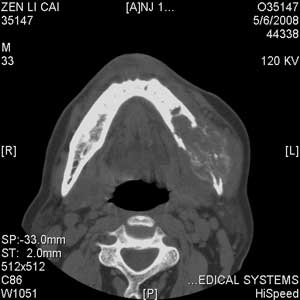

以下是引用jiangjing在2008-5-28 15:56:00的发言:[br]下颌骨左侧部骨质破坏,轻度膨胀,瘤骨形成,软组织肿胀考虑 恶性骨肿瘤-----肉瘤类